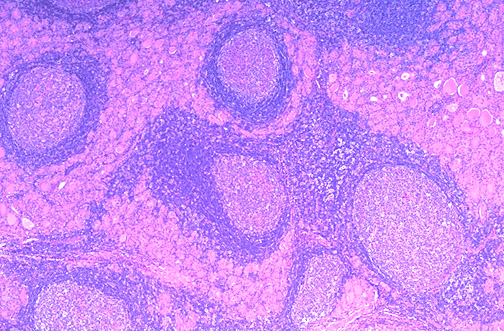

| This low power microscopic view of a thyroid with an early stage of Hashimoto thyroiditis shows prominent lymphoid follicles. This is an autoimmune disease, and often antithyroglobulin and antimicrosomal (thyroid peroxidase) antibodies can be detected in serum. Other autoimmune diseases such as Addison disease or pernicious anemia may also be present. Both thyroid growth immunoglobulins (TGI) and thyroid stimulating immunoglobulins (TSI) are present, though blocking antibodies to TSI mitigate their effect. |